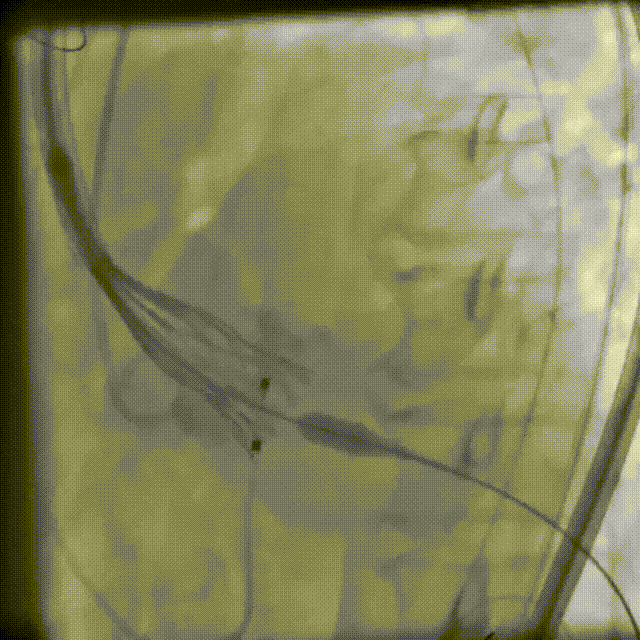

脱钩后,22mm球囊后扩,瓣膜形态改善

最终造影,无明显瓣周漏

弓部造影检查

无损伤

外周血管检查,无损伤